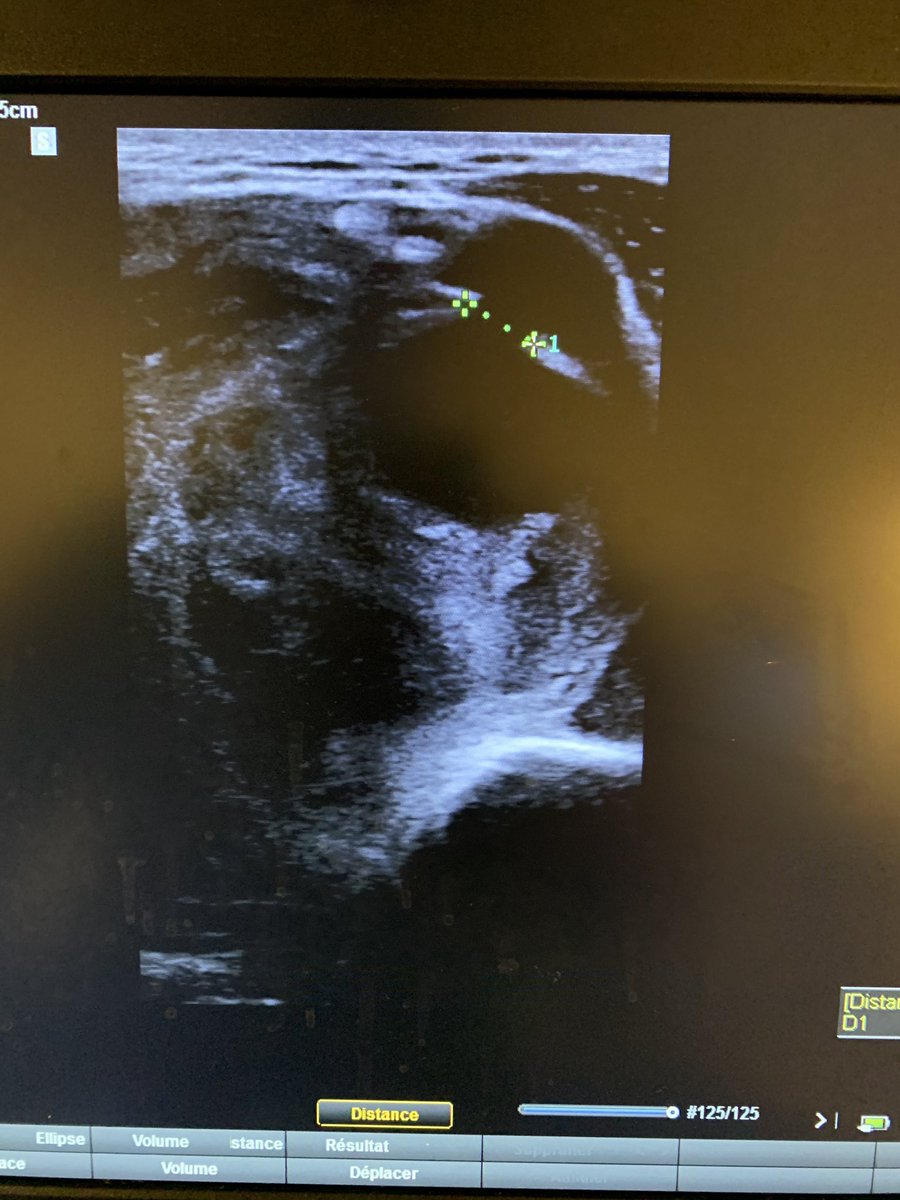

Je découvre plus haut, une brèche dans l’artère huméral, avec la formation d’un pseudo-anévrysme à très haut débit, responsable probablement de ce gros hématome.

L’échographie a changé le diagnostic, et à permis de prendre en charge efficacement le patient.

Une ponction d’hématome ici aurait sans doute été cataclysmique.